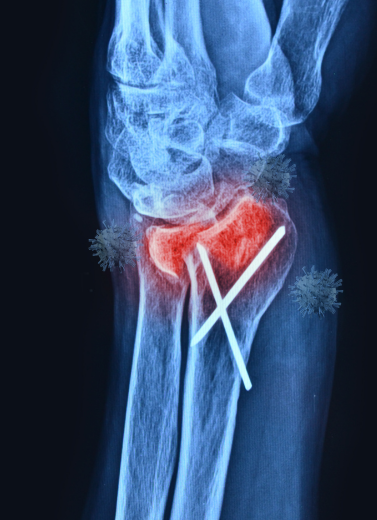

Minimally Invasive Fracture Fixation

Plating & Nailing Techniques

All surgeries are performed with infection-controlled OTs, digital X-ray support, and post-op rehab planning.